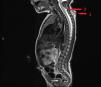

The next day, the lesion had enlarged and contained serosanguineous fluid, increasing in size in association with increasing intraabdominal pressure (Fig. 2). A cervical ultrasound scan revealed a hypoechoic tract that extended to a small area with absence of fusion of the posterior laminae. An MRI scan allowed visualization of an ascending tract that reached the thecal sac, with mild dilation at the level of C4-C5, with slight tethering of the spinal cord toward it including the meninges (Fig. 3). At 4 days post birth, the patient underwent dissection and closure of the defect. The histological examination of the specimen revealed the presence of glioneuronal tissue in the mid and deep dermis positive for S100 protein and glial fibrillary acidic protein (GFAP), in addition to a fibrous tract with cells positive for GFAP.